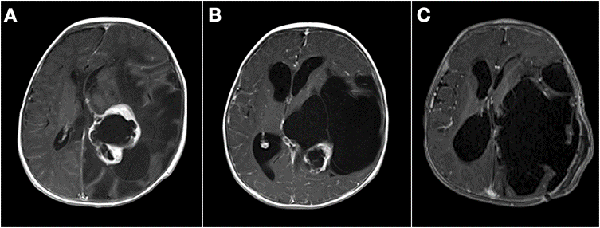

Un tema controvertido es definir cuando un tumor de SNC es congénito. Solitare et al. 14 los divide en: "definitivamente congénitos" que son aquellos que producen síntomas al nacer, "cercanamente congénitos" que son los que producen síntomas dentro de la primera semana de vida, y "probablemente congénito" que son los que se manifiestan dentro del primer mes de vida. La inclusión de pacientes de hasta 2 meses de edad fue propuesta por Arnstein et al. 1 siendo este el límite más aceptado para definir el origen congénito. Sin embargo, hay otros autores como Jellinger y Manoranjan16,17 que extienden esta definición al primer año de vida. Con base en las definiciones de los últimos dos investigadores, nuestra serie presentó 26 casos menores de un año, de los cuales solo 3 fueron menores de 2 meses de vida, todos ellos tumores embrionarios (2 indiferenciados y 1 teratoma inmaduro) (Figuras 2 y 5 B).

Figura 2: A) Paciente de 3 meses de vida, sexo masculino, consultó por macrocefalia e irritabilidad, IRM de cerebro con contraste EV donde se evidenció lesión intraventricular izquierda con extenso edema cerebral ipsilateral. Se realizó cirugía con exéresis parcial debido a labilidad hemodinámica. Anatomía patológica informó papiloma de plexos coroideos. B) IRM de cerebro 1 mes postquirúrgica. Se decidió diferir la re-exploración. C) Se realizó nueva cirugía luego de 6 meses. IRM de cerebro 1 mes post quirúrgica donde se constató la exéresis completa. Paciente evolucionó favorablemente, recuperó pautas madurativas pérdidas.